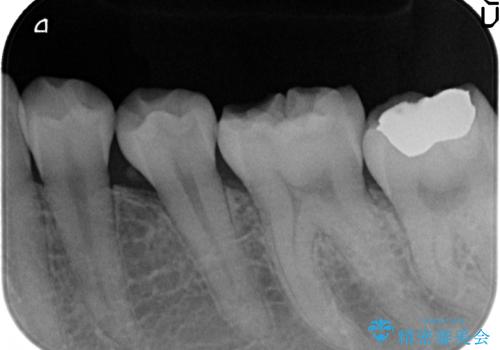

- 左下6の咬耗により歯がしみるている方の症例です。

オールセラミッククラウンによる補綴を行い、症状はなくなりました。

今回用いたオールセラミッククラウンは、ジルコニアフレームという白い素材の上にセラミックを盛っているため審美性が非常に高いのが特徴です。

またジルコニアは人工ダイヤモンドの材料にも使われているほど高い強度を持っており、そのためオールセラミッククラウンは審美性だけでなく、奥歯やブリッジの補綴も可能とするクラウンです。